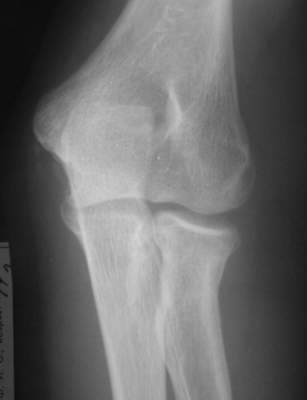

Есть методика воздействия на дистальный отломок при фиксации головки на месте - у нас - по-Марксу, у "них" - по-Паттерсону (ежели не обшибся с фамилией)... Есть методика прямого воздействия на проксимальный фрагмент... Путем пальцевого давоения... Вроде бы по-Ворохобову... у нас... Также делают и у "них"... Есть и как бы "промежуточная" методика в виде "давления" в сочетании с "накатом" - описана в каком-то вольюме JBJS, вроде бы израильскими (?) авторами... А есть еще метод по-Свинухову... Аналога у "них" мне не известно... О чрескожных манипуляциях спицами сознательно не упомянаю... Что предпочитаете? ------------------------- А вот case report... Подросток 14 лет... Зкрытая репозиция "давление-накатом"... Безрезультатно... Через 3 дня репозиция по-Свинухову... Вроде бы все закончилось успешно... Однако 6 мес спустя после 2-кратного курса реабилитации клническая картина достаточно плачевна: Ротация предплечья: справа (здоровая) - 80 кнутри и 85-90 кнаружи слева (больная) - 40 кнутри и 40 кнаружи При этом клинически внутренняя ротация справа (здоровая сторона) и слева (больная сторона) составляет порядка 85 и 80-75 соответвенно, но за счет ротационной мобильности запястья, порядка, например, 40-35 градусов на больной стороне... Сгибание слева (травмированная сторона) - 90 гр. разгибание - около 160 гр. Рентгенологически: в боковой проекции гетеротопическая оссификация по передней поверхности локтевого сустава, над головкой луча с "шипом" над радиокапителлярным сочленением... однако в прямой проекции локализация оссификата трудно определима, хотя вроде бы располагается по ходу сухожилия бицепса, т.е. в проекции луче-локтевого сочленения, но со стороны локтевой кости.... Что делать? Кто виноват? :-)